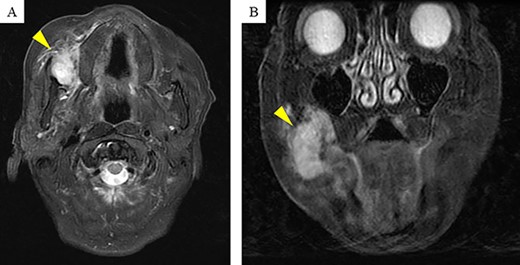

Computerized tomography showed a mass, measuring 31 × 25 × 30 mm, located in the right buccal mucosa. On magnetic resonance imaging, contrast-enhanced T2-weighted images showed a high signal (Fig. 3A and B).

Magnetic resonance imaging (MRI) findings: contrast-enhanced T2-weighted MRI shows a high signal mass (arrow head) of size 31 × 25 × 30 mm in the right buccal mucosa.